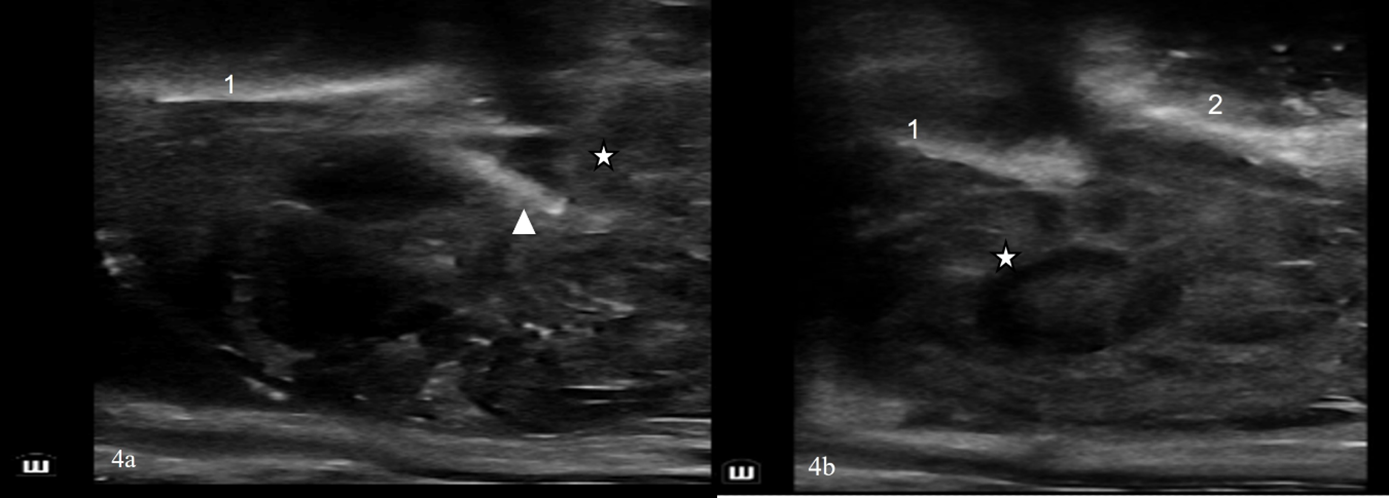

El examen ecográfico externo de la hemipelvis izquierda mostró una fractura aguda, completa y desplazada (aproximadamente 7 cm) en el margen caudal del ala ilíaca izquierda y de la cara craneal del cuerpo ilíaco (figuras 2). El examen de la hemipelvis derecha también evidenció una fractura desplazada del ala ilíaca derecha, ubicada más cerca del plano medio que la izquierda. El contorno del hueso ilíaco derecho se presentó más liso, irregular y grueso; estas características sugerían cambios de remodelación ósea crónica (figuras 3). El abordaje ultrasonográfico transrectal reveló un hematoma ventral y un fragmento óseo a la altura de la articulación sacroilíaca derecha (figuras 4).